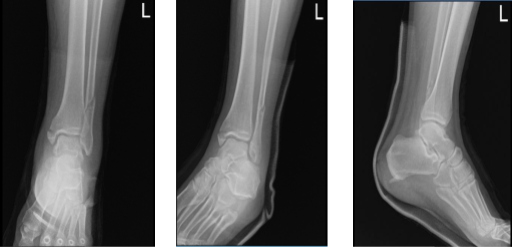

Case Study: ORIF: Lateral Malleolus Plate and

Interfragmentary Screw, Medial Malleolus Screws

using Fluoroscopy in a 60 year-old male

Left ankle X-ray complete 3 or more views